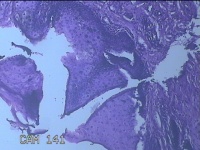

右下唇肿物

性别

女

年龄

12岁

临床诊断

唇囊肿

一般病史

右下唇部肿物一月余。

标本名称

大体所见

灰白粉红色肿物0.8x0.7x0.2cm一个,表面光滑。

图2